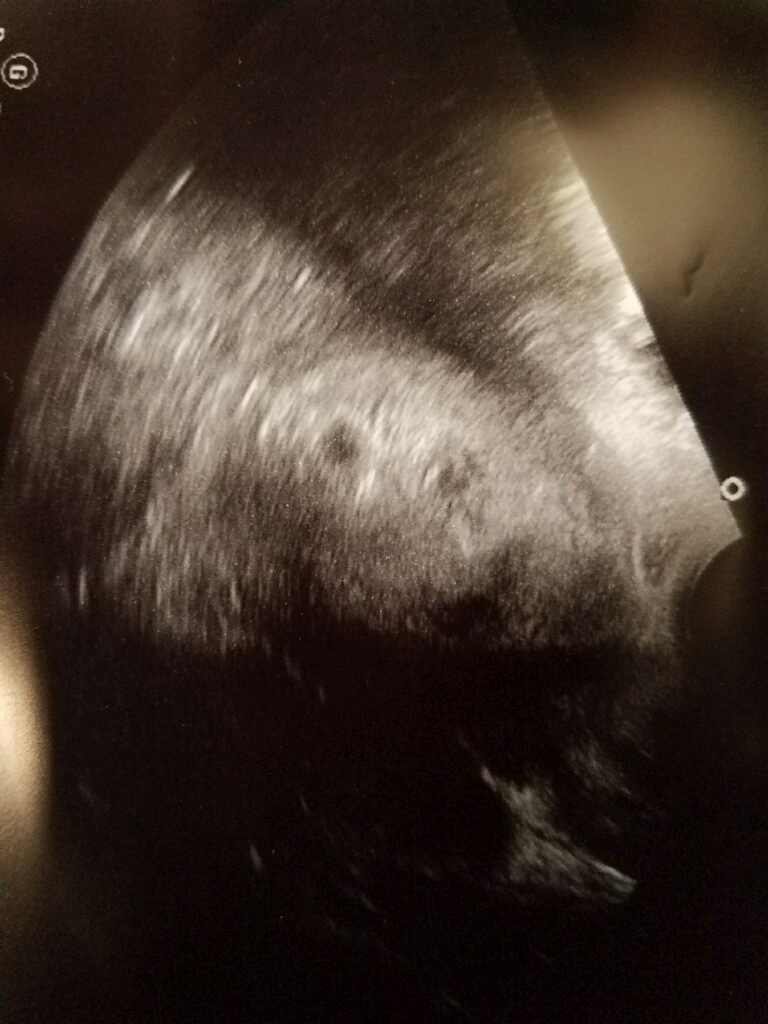

sono -1 or 2? - updated

dr said this is 1 i see 2

update- there was only 1 today ! no sign of a second. guess it was just too early, dr didnt say anything and we didnt ask what it could have been.

That's twins! I would bet money on it! Either way Congrats! Looks very similar to my first ultrasound at 5 weeks! Looks like two sacs! I would bet money its two!!! Congrats!! If you have twin questions let me know I survived 6 months as of today lol